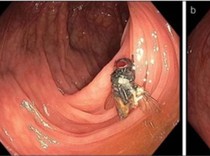

Keluhkan Napas Bau, Ternyata Dokter Temukan Kecoak Mati di Tenggorokan Pasien Rabu, 04 Sep 2024 21:00 WIB